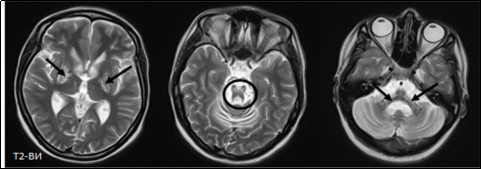

Характерным МРТ-паттерном при БГШ принято считать овальную симметричную гиперинтенсивную зону в области бледного шара внутри более обширной гипоинтенсивной зоны. Этот типичный симптом БГШ назван «глазом тигра», и его формирование связано с внеклеточным накоплением железа в базальных ганглиях [32]. В русскоязычной литературе встречаются единичные публикации, посвященные этой крайне редкой патологии, в которых подчеркивается сложность ее диагностики как у детей, так и у взрослых [6]. Лечение БГШ не существует — заболевание некурабельно. В связи с этим лечение данной патологии носит только симптоматический характер. На рисунке 2 представлено характерное отложение железа в бледном шаре с симптомом «глаза тигра» при ННЖМ-1 на МРТ.

Рис. 2. МРТ при ННЖМ-1. Отложение железа в бледном шаре с симптомом «глаза тигра» (стрелки)

Еще одно заболевание, рассматриваемое нами в исследовании, — это болезнь Вильсона — Коновалова, вызванная мутациями в генах ATP7B [10]. Гепатолентикулярная дегенерация (или болезнь Вильсона — Коновалова) — орфанное аутосомно-рецессивное наследственное заболевание метаболизма меди с глобальной распространенностью около 1/100 000–3/100 000 населения, проявляющееся преимущественно печеночными, неврологическими и психиатрическими нарушениями вследствие чрезмерного отложения меди в органах и тканях [14]. На рисунке 3 представлены изменения на МРТ головного мозга у пациента с БВК: симметричное повышение интенсивности МР-сигнала от подкорковых структур, среднего мозга, с выраженной атрофией ствола мозга, средних мозжечковых ножек и полушарий мозжечка; признаки вторичной дегенерации мосто-мозжечковых путей в варолиевом мосту (симптом «креста»).

Рис. 3.МРТ-исследование в режиме Т2-ВИ (аксиальные срезы) пациентки М.